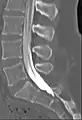

Computed tomography after conventional myelography. The overlap-free representation often allows a more secure assessment. The high density of contrast material may be troublesome in case of insufficient mixing prior to CT.